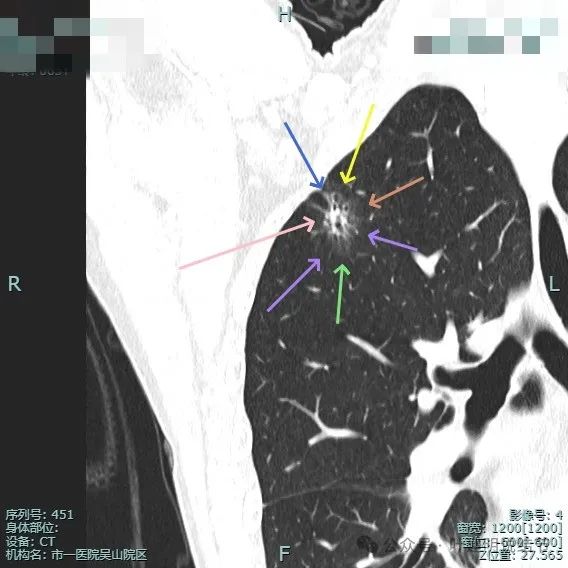

病灶混合密度,毛刺典型,灶内密度紊乱,表面分叶,有较多小空泡征,胸膜略有牵拉。

血管进入病灶,磨玻璃成分较淡,边缘不平毛糙多毛刺、胸膜有牵拉,表面分叶征明显。

实性成分较多,表面不平,磨玻璃部分较淡,血管进入与穿行,胸膜牵拉可见,距其不远有次病灶也是淡磨玻璃密度,轮廓较清,也考虑是肿瘤范畴的,当然风险仍低。

表面不平分叶,实性成分明显,灶内细支气管扩张。

此视角看是典型的浸润性腺癌影像表现:混合密度、毛刺锐利典型、表面分叶、边缘不平、灶内实性成分明显且整体显得杂乱、病灶内部明显扩张的细支气管,磨玻璃成分与正常肺组织之间边界清楚,整体轮廓也清楚。

血管进入以及胸膜牵拉,灶内小空泡征与密度显杂乱,次病灶也有血管进入。

实性成分较明显,扩张的支气管壁显得僵硬,表面分叶明显,边缘细毛刺明显。

毛刺征、混合密度且实性成分杂乱、支气管扩张僵硬、分叶征明显。

血管进入、表面分叶、胸膜牵拉、磨玻璃成分明显、实性部分缺乏收缩力但显杂乱,整体轮廓与边界清。